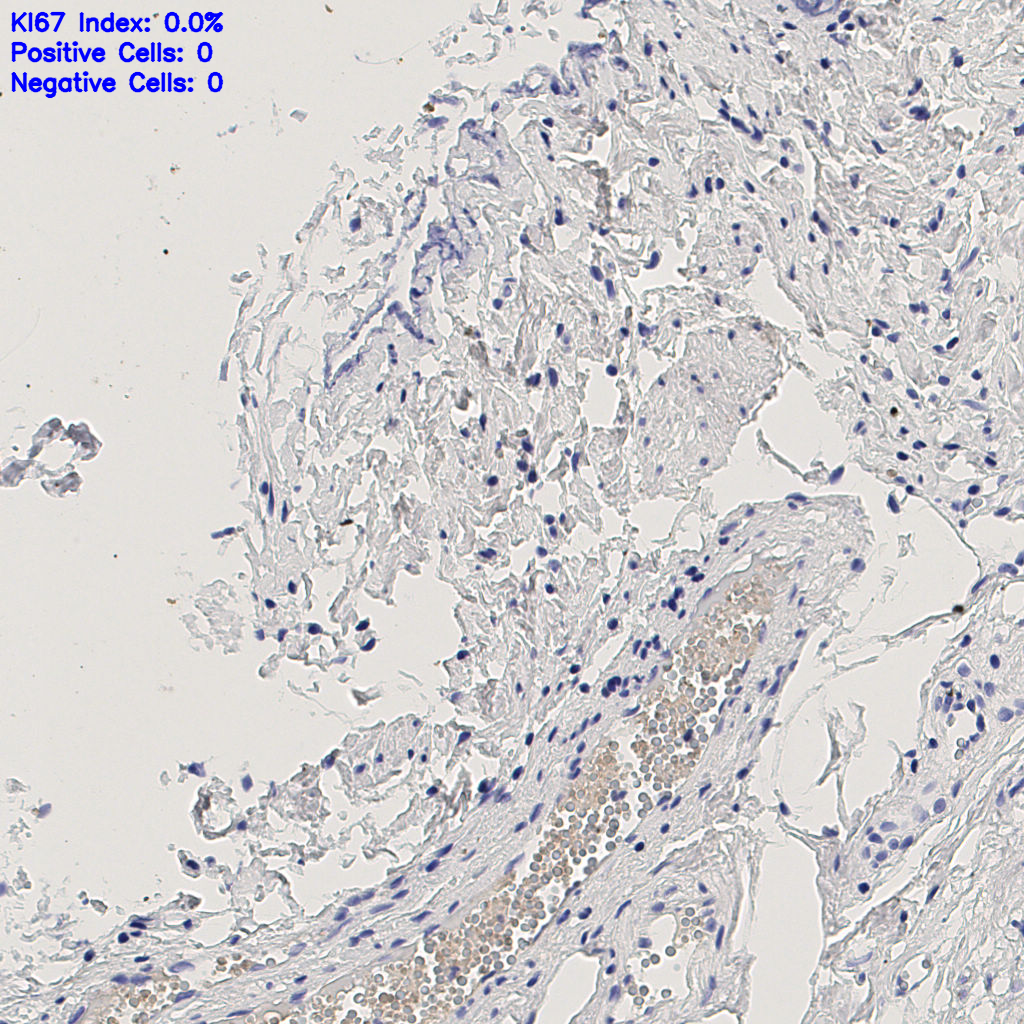

H255858-KI-67.ndpi

slice_49_3_x43904_y2688.png

slice_49_4_x43904_y3584.png

slice_49_5_x43904_y4480.png